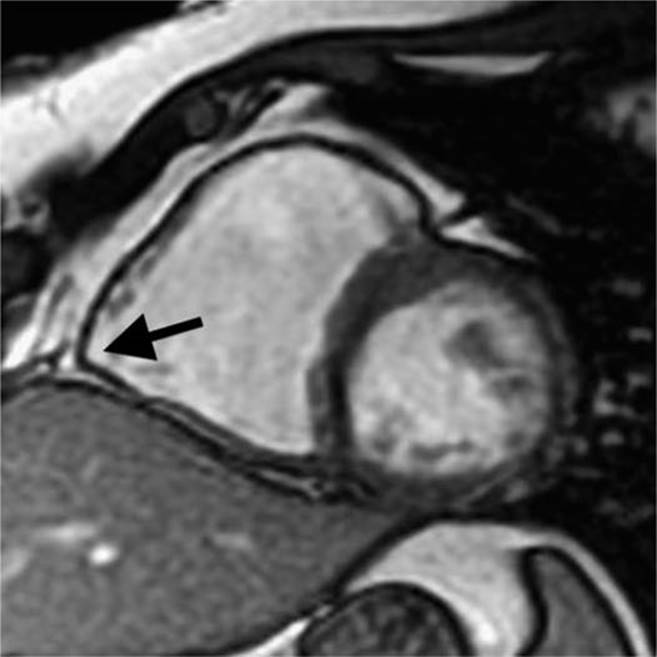

A 21-year-old competitive triathlete was brought into the emergency department after collapsing during a local race. She reported the onset of a rapid heart rate near the finish line of the cycling portion and suddenly collapsed. Upon arrival, the emergency medical services found her to be in sustained ventricular tachycardia (VT) at 260 ms (Figure 54-1), and she was converted to sinus rhythm with a 200 J external shock. Upon arrival to the emergency room, she was found again to be in VT at 263 bpm with left bundle branch block (LBBB), superior axis morphology. She lost consciousness and was again externally cardioverted (Figure 54-2). A 12-lead electrocardiogram (ECG) (Figure 54-3) demonstrated T-wave inversions across the precordium. An echocardiogram revealed no evidence of structural heart disease. Due to her ECG abnormalities, this was followed up with cardiac MRI, which revealed a dilated right ventricle (RV) with akinetic segments in the RV free wall and base (Figure 54-4). She was taken for electrophysiology study (EPS) which demonstrated easily inducible VT with two different morphologies (LBBB superior axis, and LBBB indeterminate axis) (Figure 54-5). Ablation was attempted but was unsuccessful in eliminating all inducible VTs. An epicardial focus was suspected. Based upon her evaluation, she was found to meet diagnostic criteria for arrhythmogenic right ventricular dysplasia/cardiomyopathy (ARVD/C). She was implanted with a single chamber ICD and discharged on β-blockers. During follow-up, frequent symptomatic runs of NSVT were recorded by her ICD. Antiarrhythmic drug therapy was discussed with the patient, but she preferred not to take more medications. For this reason, an epicardial VT ablation procedure was performed. Her VT was mapped to the anterior lateral RV free wall and ablated successfully (Figure 54-6). She did well following her ablation procedure and remained VT-free. She was advised to give up participation in athletic activities. She was also referred to a genetic counselor for genetic counseling and testing. Upon inquiry, it was noted that her maternal grandfather died suddenly of a “heart attack” in his 40s. No other details were known, and there was no other history of cardiomyopathy or sudden death. Genetic testing returned a pathogenic mutation in the plakophilin-2(PKP2) gene: 2146-1G>C. Her older brother, also an athlete, was tested and found also to carry this mutation and was scheduled for appropriate cardiac screening.

FIGURE 54-4 Cardiac MRI notes a dilated RV with akinesis of the base of the RV. Outpouching of the angle of the RV (denoted by arrow) is a classic MRI finding in ARVD/C.